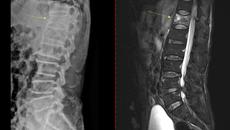

기침 한번 했는데 골절…목숨 앗아가는 침묵의 '이 질환'

[서울=뉴시스] 류난영 기자 = 골다공증은 '골다공'이라는 말 그대로 뼛속에 구멍이 생기는 질환이다. 뼛속에 구멍이 나 뼈의- 2026-01-07 01:01